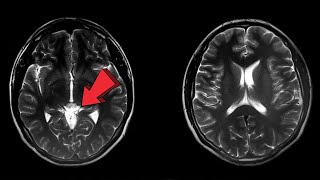

Brain Scan Captures Final Moments Before Death: Is Life Flashing BeforeYour Eyes Real? #DyingBrain First Brain Scan of Dying Man Reveals a Unexpected Secret !

Brain Scan Captures Final Moments Before Death: Is Life Flashing BeforeYour Eyes Real? #DyingBrain First Brain Scan of Dying Man Reveals a Unexpected Secret !